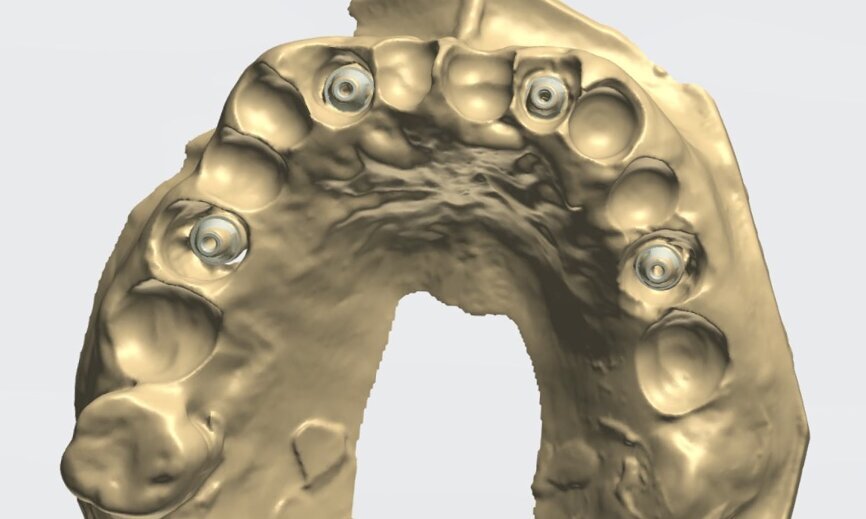

To design the prosthesis digitally, we first selected the screw-retained abutment (SRA) angle and gingival height (Fig. 14) and then we created the patient model on which we could connect the BLX implants with the SRAs selected from the Straumann library (Fig. 15). The implant placement guide was on the model, leveraging the high stability that we could gain from palatal support (Figs. 16 & 17). After printing the model, the BL  implant analogues were positioned using the template for navigation. The digital planning using coDiagnostiX (Version 9.14) allowed the dental technician to identify all the necessary parameters related to implant position (Figs. 18–22). Emergence profiles were set-up on the model (Fig. 23). The model was scanned using scan bodies, and a CAD/CAM temporary restoration was designed and milled in a PMMA-based restorative material (Figs. 24–29).